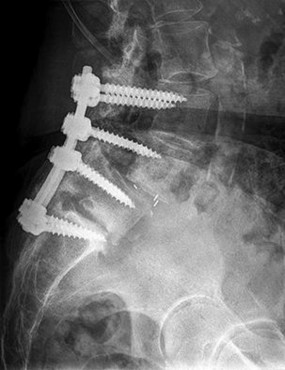

The patient is treated by another physician and undergoes the procedure shown in Figures 40a and 40b. She currently cannot stand upright. Spinopelvic measurements reveal her pelvic incidence to be 85 degrees and pelvic tilt to be 40 degrees. Her lordosis from T12-S1 is 35 degrees. Which additional surgical procedure should be considered?

40A

B